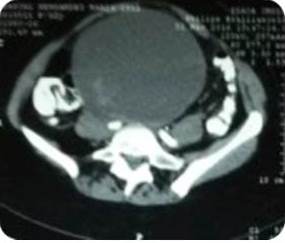

Paciente de 53 años de edad, III gestas, III paras, quien refiere aumento de volumen en hipogastrio, progresivo de seis meses de evolución motivo por el cual acude al Centro Médico Docente la Trinidad, donde es evaluada. Al examen físico: paciente en buenas condiciones, masa abdominal palpable desde hipogastrio que sobrepasa cicatriz umbilical, móvil, no dolorosa, aumentada de consistencia. Dentro de los estudios paraclínicos, se encontró un Ca125: 325 U/mL, resto sin alteraciones. Se solicita tomografía de abdomen y pelvis con doble contraste, evidenciando un LOE de gran tamaño (Figura 3). Paciente es intervenida quirúrgicamente, se le practicó una incisión de Maryland, evidenciando como hallazgo intra-operatorio: tumor de ovario izquierdo gigante, con infiltración macroscópica de superficie ovárica (Figura 4), se procede a realizar protocolo de ovario. El resultado patológico obtenido fue biopsia ovario izquierdo: tumor seroso papilar borderline (de bajo grado de malignidad) con foco de micro-invasión menor a 1 mm, tumor seroso borderline en superficie ovárica - cuerpos de psamoma. Biopsia ovario derecho: tumor seroso papilar borderline - cuerpos de psamoma. Epiplón mayor: implante superficial no invasivo de tumor seroso borderline, fondo de saco anterior: implante no invasivo de tumor seroso papilar borderline. Resto de las muestras sin alteraciones. Paciente no recibe quimioterapia. Se observa disminución de Ca125 hasta su normalidad y ausencia de enfermedad en estudios radiológicos de control. Actualmente sin evidencia de enfermedad, seis meses pos operatorio.